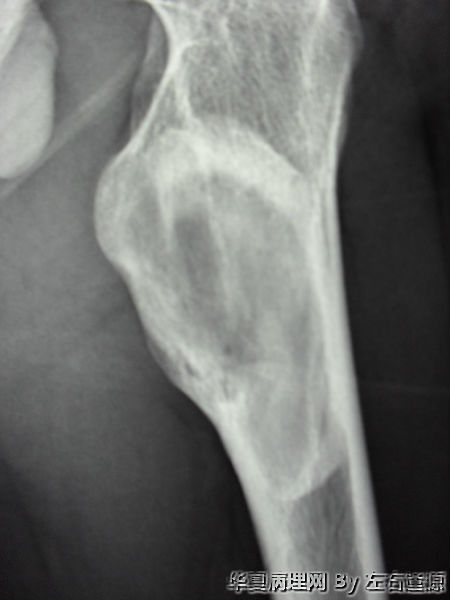

男19岁 左股骨上段异常增殖

• 男19岁 左股骨上段异常增殖图3

图3

骨纤维结构不良

同意纤维结构不良,而不是骨纤维结构不良。

纤维结构不良。

X线可见病变界限较清,应考虑骨化性纤维瘤。

“纤维结构不良”和“骨纤维结构不良”确实不是一个概念,后者骨小梁周围有骨母细胞,并且有特殊的发病部位。本例骨小梁周围大部分没有骨母细胞,是纤维结构不良。,而不是骨纤维结构不良。